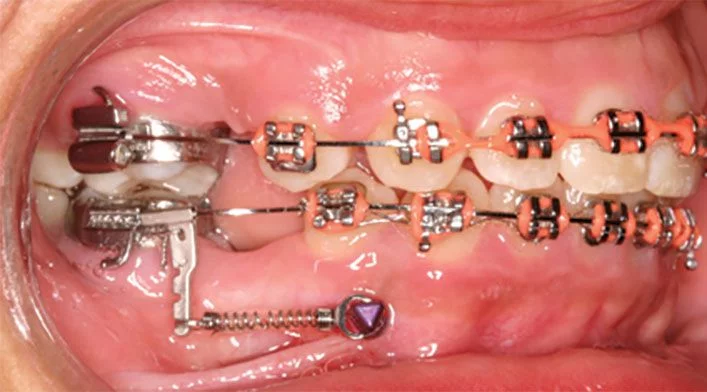

Mini-vis TAD pour asymétries dentaires et protraction

Asymétries dentaires et faciales

Désalignement de la ligne médiane dentaire ou inclinaison du plan occlusal. Les TADs corrigent le plan et repositionnent les dents par rapport au visage.